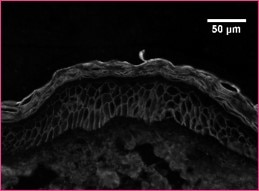

Immunohistochemical staining of stromal protein expression in DCIS with sclerotic or myxoid stromaMicrophotographs displaying HE staining (A-B), and IHC staining for biglycan (C-D), decorin (E-F) and versican (G-H). ...read more